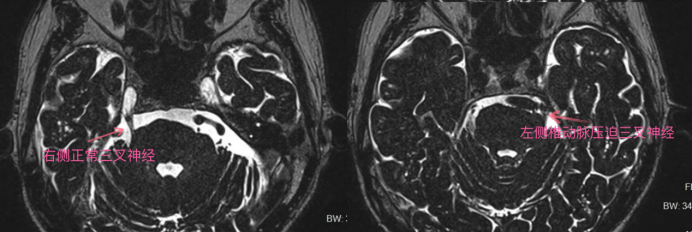

黄陂区人民医院放射影像科二区针对三叉神经痛开展的三叉神经磁共振检查,能获得高信噪比、高空间分辨率的图像,便于观察三叉神经与其邻近血管之间的关系,同时也能判断附近是否有肿瘤占位挤压,有助于明确三叉神经痛及面肌痉挛的病因,为临床治疗及手术提供诊断依据。